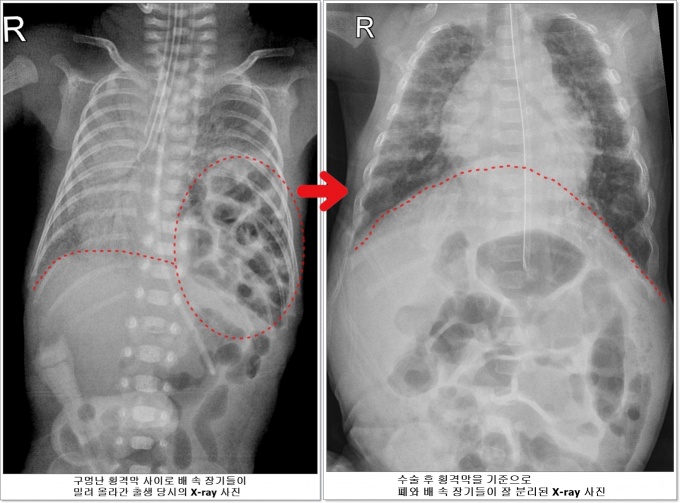

Ⱦ°Ý¸·Àº °¡½¿°ú ¹è¸¦ ³ª´©´Â ±ÙÀ°À¸·Î ¼±Ãµ¼º Ⱦ°Ý¸· Å»ÀåÁõÀº ±¸¸Û ³­ Ⱦ°Ý¸· »çÀÌ·Î ¹è ¼Ó Àå±â°¡ ¿Ã¶ó°¡ ½ÉÀå°ú Æó¸¦ ¾Ð¹ÚÇÏ´Â ÁßÁõ ÁúȯÀÌ´Ù.

Ãâ»ý ÈÄ ½Å»ý¾Æ´Â ½ÉÇÑ È£ÈíºÎÀüÀ¸·Î ÀÎÇØ ÀΰøÈ£Èí±â¿Í ¿¡Å©¸ð(ECMO) Ä¡·á°¡ ÇÊ¿äÇÏ´Ù. ±¸¸Û ³­ Ⱦ°Ý¸· »çÀ̸¦ ÅëÇØ ¿Ã¶ó°£ ¼ÒÈ­±â Àå±â¸¦ ¹è ¼ÓÀ¸·Î ³»¸®°í ±¸¸ÛÀ» ¸·´Â ¼ö¼úÀ» ¹Þ¾Æ¾ß ÇÑ´Ù.

È£»ïÀÌ´Â ÀÌ ¸ðµç °úÁ¤À» ´Ù À̰ܳ»°í ž Áö 40ÀÏÀÌ µÇ´ø 5¿ù20ÀÏ Ã¼Áß 1530gÀÌ µÇ¸é¼­ ¼Ò¾Æ¿Ü°ú ³²±ÃÁ¤¸¸ ±³¼ö°¡ ±¸¸Û³­ Ⱦ°Ý¸·À» ¸·´Â ¼ö¼úÀ» ¼º°øÀûÀ¸·Î ½ÃÇàÇß´Ù.